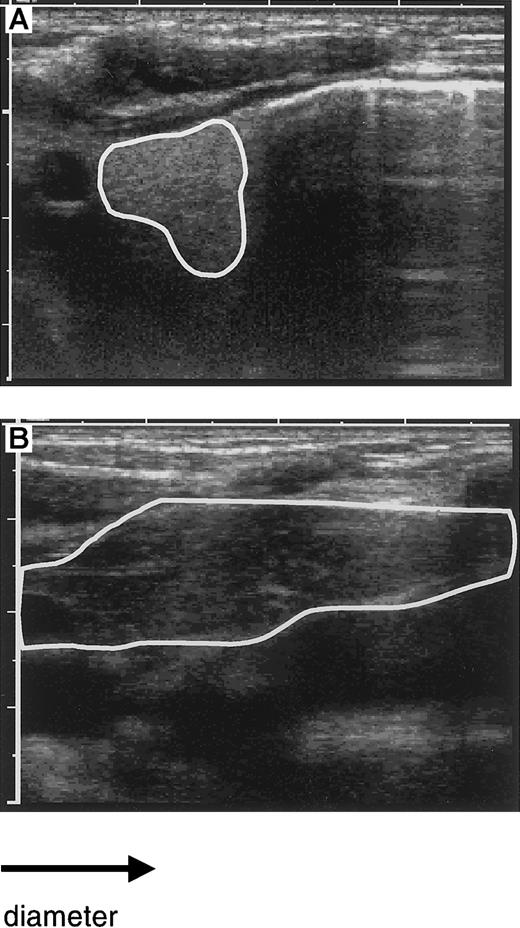

To detect an increase in thymic size and to correlate this change with peripheral reconstitution of the T-cell compartment, sequential studies of the thymus by ultrasound were performed in 9 of the 10 patients in whom T-cell reconstitution was studied. An example of the visualization of the thymus by ultrasound before and after transplantation is shown in Figure 2. A normally sized thymus with a retrosternal lobe more than 3 cm in diameter was observed during the third to fifth month in the patients, coinciding with increasing numbers of CD4+CD45RA− cells in the blood (Figure3). In 5 patients, the time point of ultrasound studies allowed us to detect an early increase of the thymic size, as defined by a visible but still abnormally small retrosternal lobe (< 3 cm). This coincided in 3 of the 5 patients with the initial appearance of very low numbers of CD45RA+ cells, whereas in 2 patients these cells appeared only shortly thereafter. These findings indicate that the increase of the thymic size preceded the appearance of CD4+ cells.

Evaluation of thymic size by ultrasound.

The size of the left retrosternal thymic lobe as visualized by ultrasound is circumscripted: before transplantation with a diameter of 1 cm (A) and after transplantation with a diameter of more than 4 cm (B). Note the enhanced density before transplantation with normalization after transplantation.